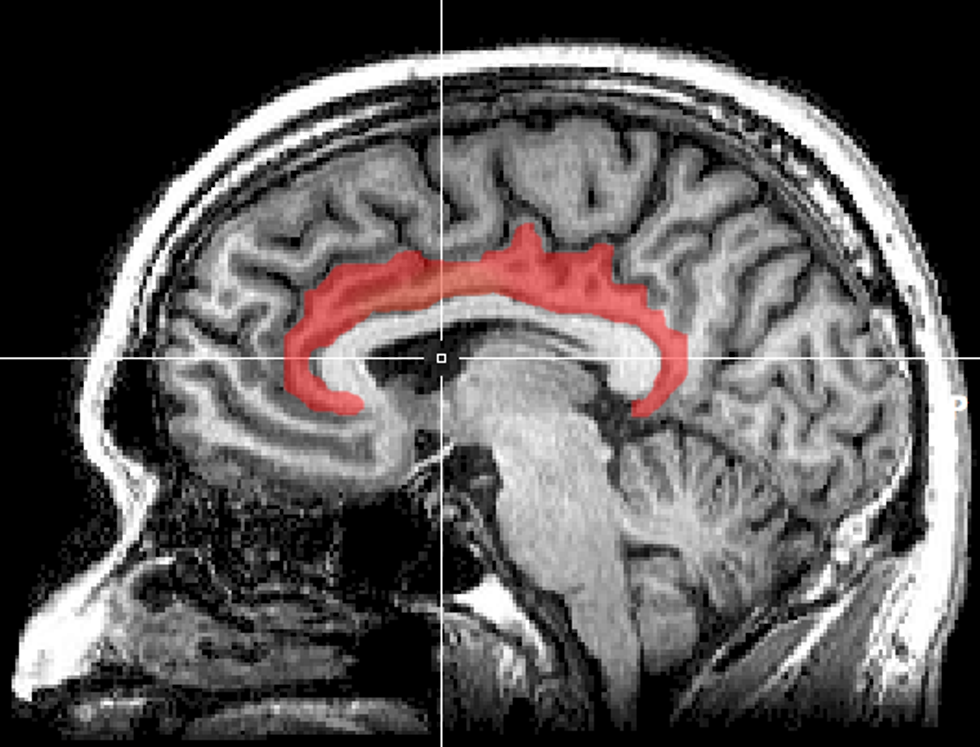

An MRI and blood draw afterward gave Maninger and Bales a peek at the animal's brain, and in addition to higher testosterone and stress hormones, two more areas deep within his brain were triggered. The first, the cingulate cortex, has a lot to do with social rejection. The second, the lateral septum, is connected to bonding.

"The approximate locations of the cingulate cortex (red) and lateral septum (green) in an MRI of the human brain.

Original image from Geoff B Hall/Wikimedia Commons.